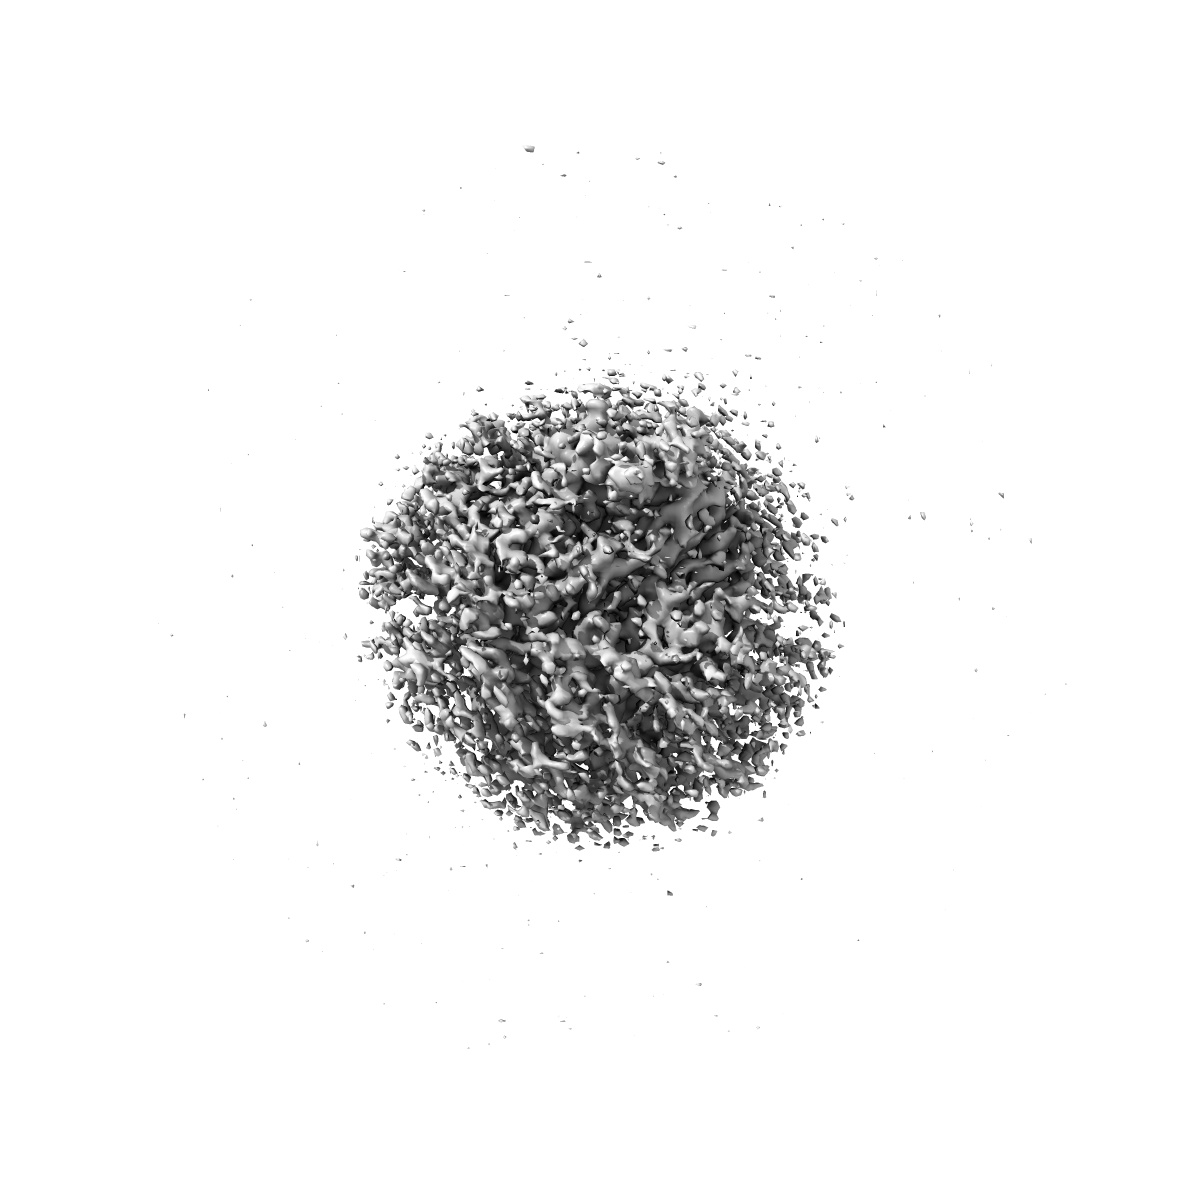

Cryo-EM structure of human TauT in presence of taurine, determined in an inward-facing occluded conformation

Sample: Complex of human Taurine Transporter with taurine

Transport and inhibition mechanism for human TauT-mediated taurine uptake.

Chao Y, Zhou Z, Xia H, Yang C, Li T , Tang YQ, Shu Y , Ba Q, Hong J , Li D , Qu Q

(2025) Cell Res , 35 , 381 - 384